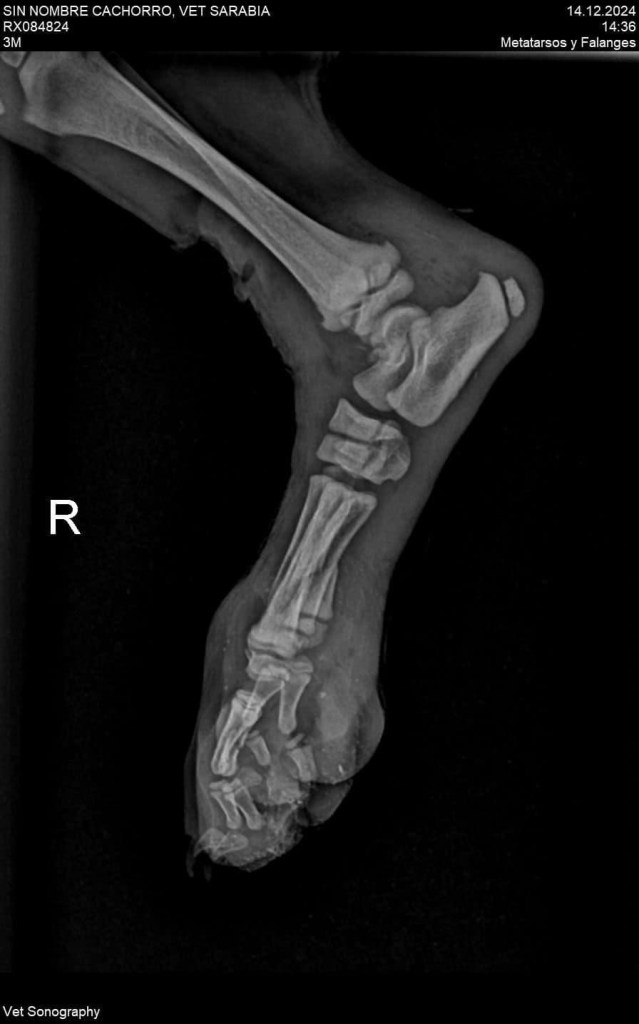

El cachorrito tiene fracturada una patita y necesita una cirugía que cuesta más de 5 mil pesos. Comparten su número de cuenta para quienes deseen colaborar con la recuperación y ayudar a este pobre cachorrito 😭🙏❤️🩹